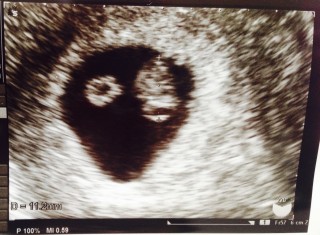

初診でした! 10月に枯死卵のまま繋留流産したので、エコー見る時怖くてたまりませんでしたが、3歳の娘ががんばって!と手を握ってくれてました(泣) 最初、袋しかわからず、またしても!と思いましたが赤ちゃんいてくれました。 心拍もわかりますよ~と言われ一安心しました